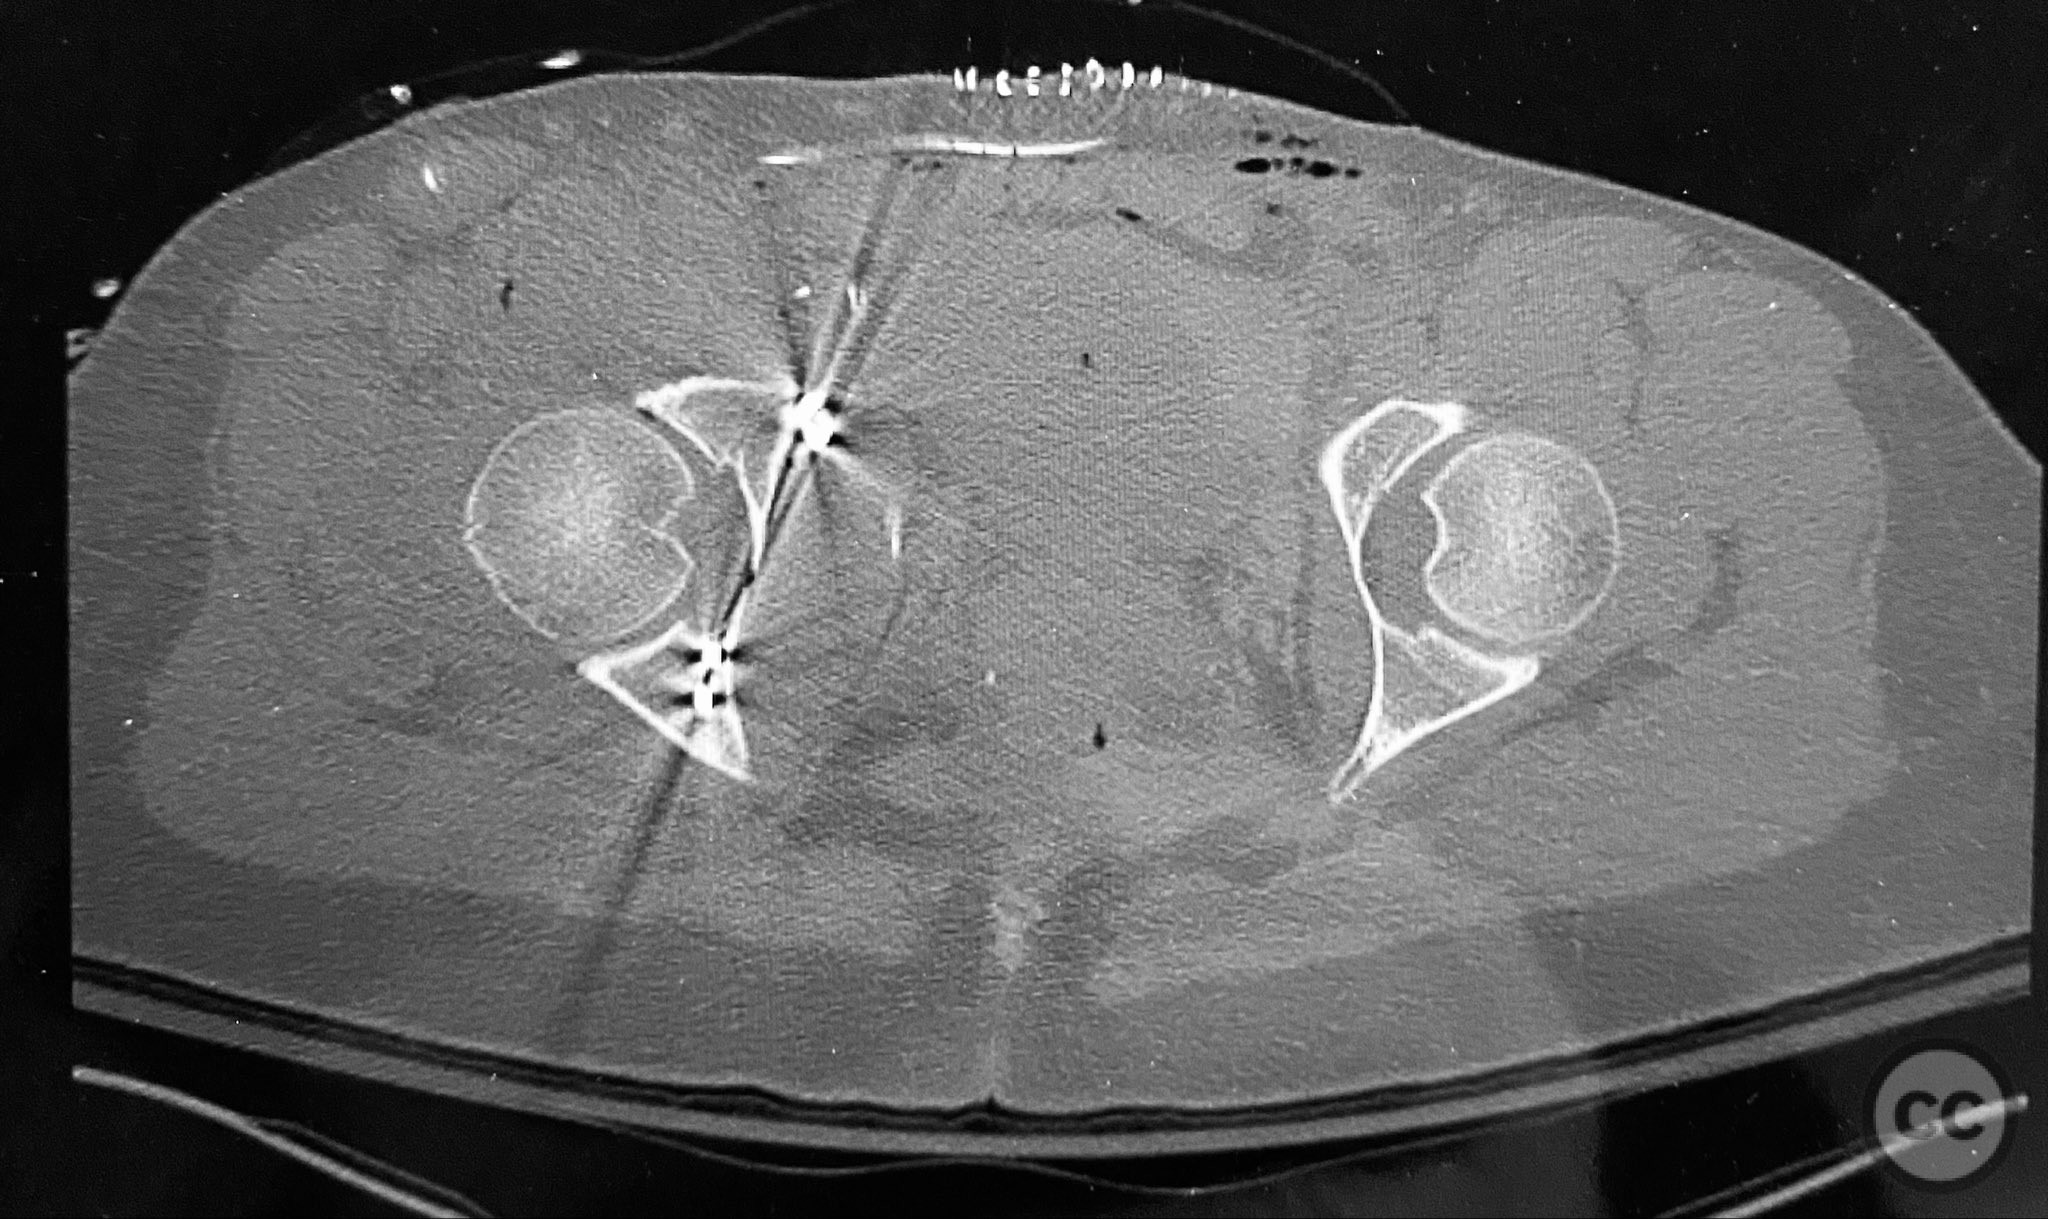

Clinical and radiological findings:  The patient sustained a complex both column acetabular fracture, AO/OTA 62C1, characterized by several large columnar fragments, an independent anterior inferior iliac spine (AIIS) fragment, a notable dome fragment predominantly attached to the posterior wall (PW) fragment, and a distinct parasymphyseal injury zone. Initial application of a pelvic binder resulted in increased displacement of the fracture fragments. Preoperative imaging, including surface renderings and multiplanar CT, demonstrated the independent AIIS fragment, detailed cortical surfaces, and the orientation of fracture planes. The majority of the acetabular dome was associated with the PW fragment, a critical detail for surgical planning and reduction.

The anterior column fragment was reduced first under direct visualization and held with a 6-hole plate and lag screw. The 12-hole intrapelvic plate was then contoured and applied along the pelvic brim to reinforce the reduction. The posterior column and posterior wall fragments, including the dome component, were stabilized with lag screws placed through safe osseous corridors under fluoroscopic guidance. The independent AIIS fragment was addressed during the exposure and incorporated into the reduction construct. The parasymphyseal injury zone was inspected for stability following fixation. Postoperative CT confirmed anatomical reduction and stable fixation of all fragments.

Orthopaedic implants used:   6-hole reconstruction plate, 12-hole intrapelvic plate, multiple lag screws